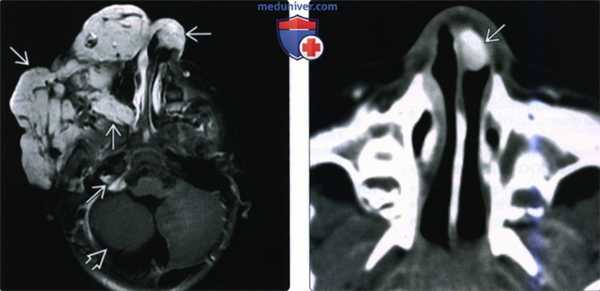

(Слева) При аксиальной МРТ Т1ВИ С+ FS у четырехмесячной девочки с синдромом PHACES в правом околоушном пространстве, задненижних отделах правой глазницы, правой щеке, носу, внутреннем слуховом канале и в области правого мостомозжечкового угла визуализируются множественные гемангиомы, накапливающие контраст. Обратите также внимание на гипоплазию правой гемисферы мозжечка.

(Справа) При аксиальной КТ с КУ у семимесячного ребенка с опухолью носа визуализируется объемное образование, интенсивно накапливающее контраст, и вызывающее окклюзию преддверия носа слева. Все характеристики и расположение этого образования типичны для МГ.